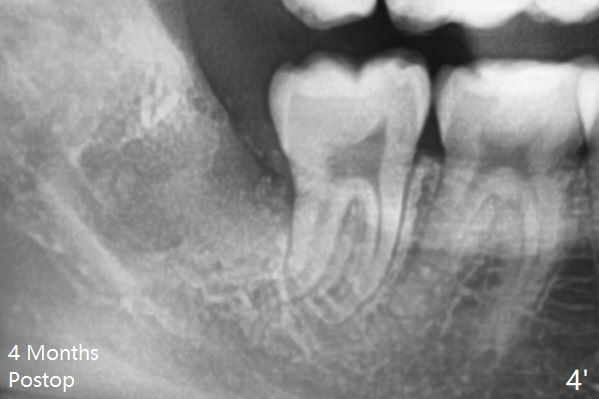

The bone density increases and becomes even at #32 sockets 4 months postop (Fig.4').